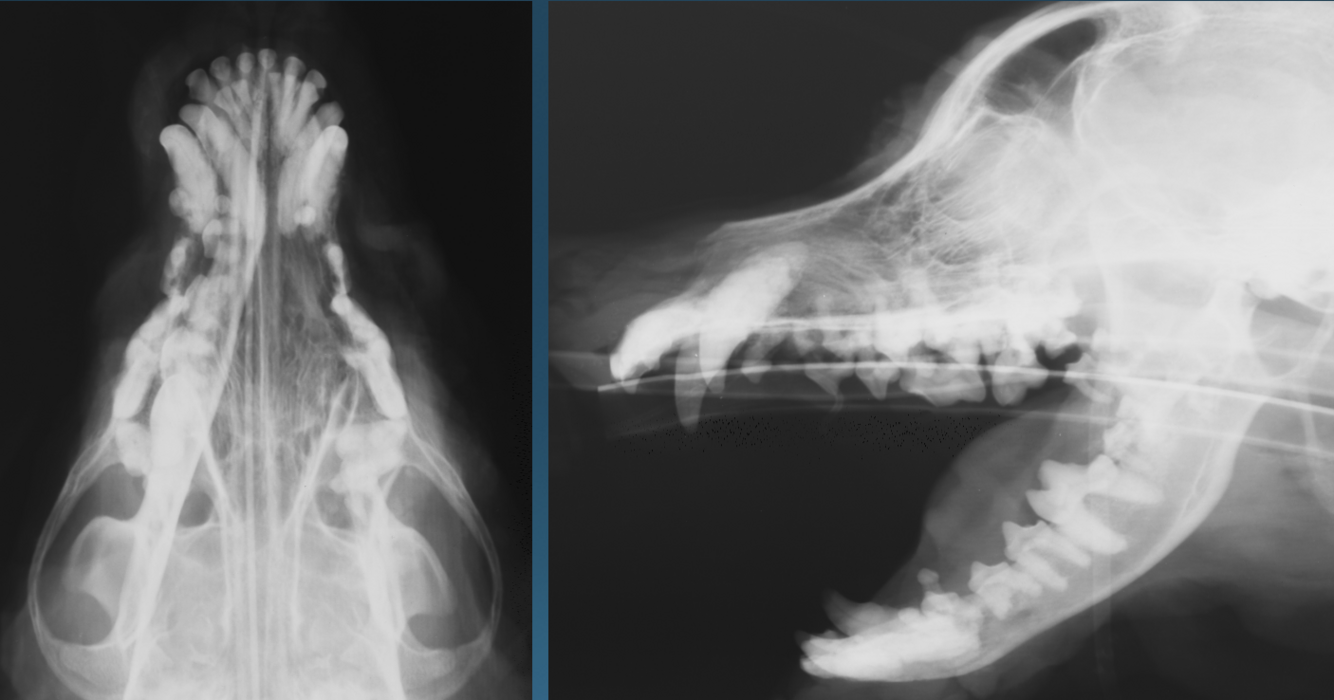

What is shown in these images?

soft tissue neoplasia invading the skull:

-loss of left hemimandible seen on VD

-large associated soft tissue mass seen on oblique view